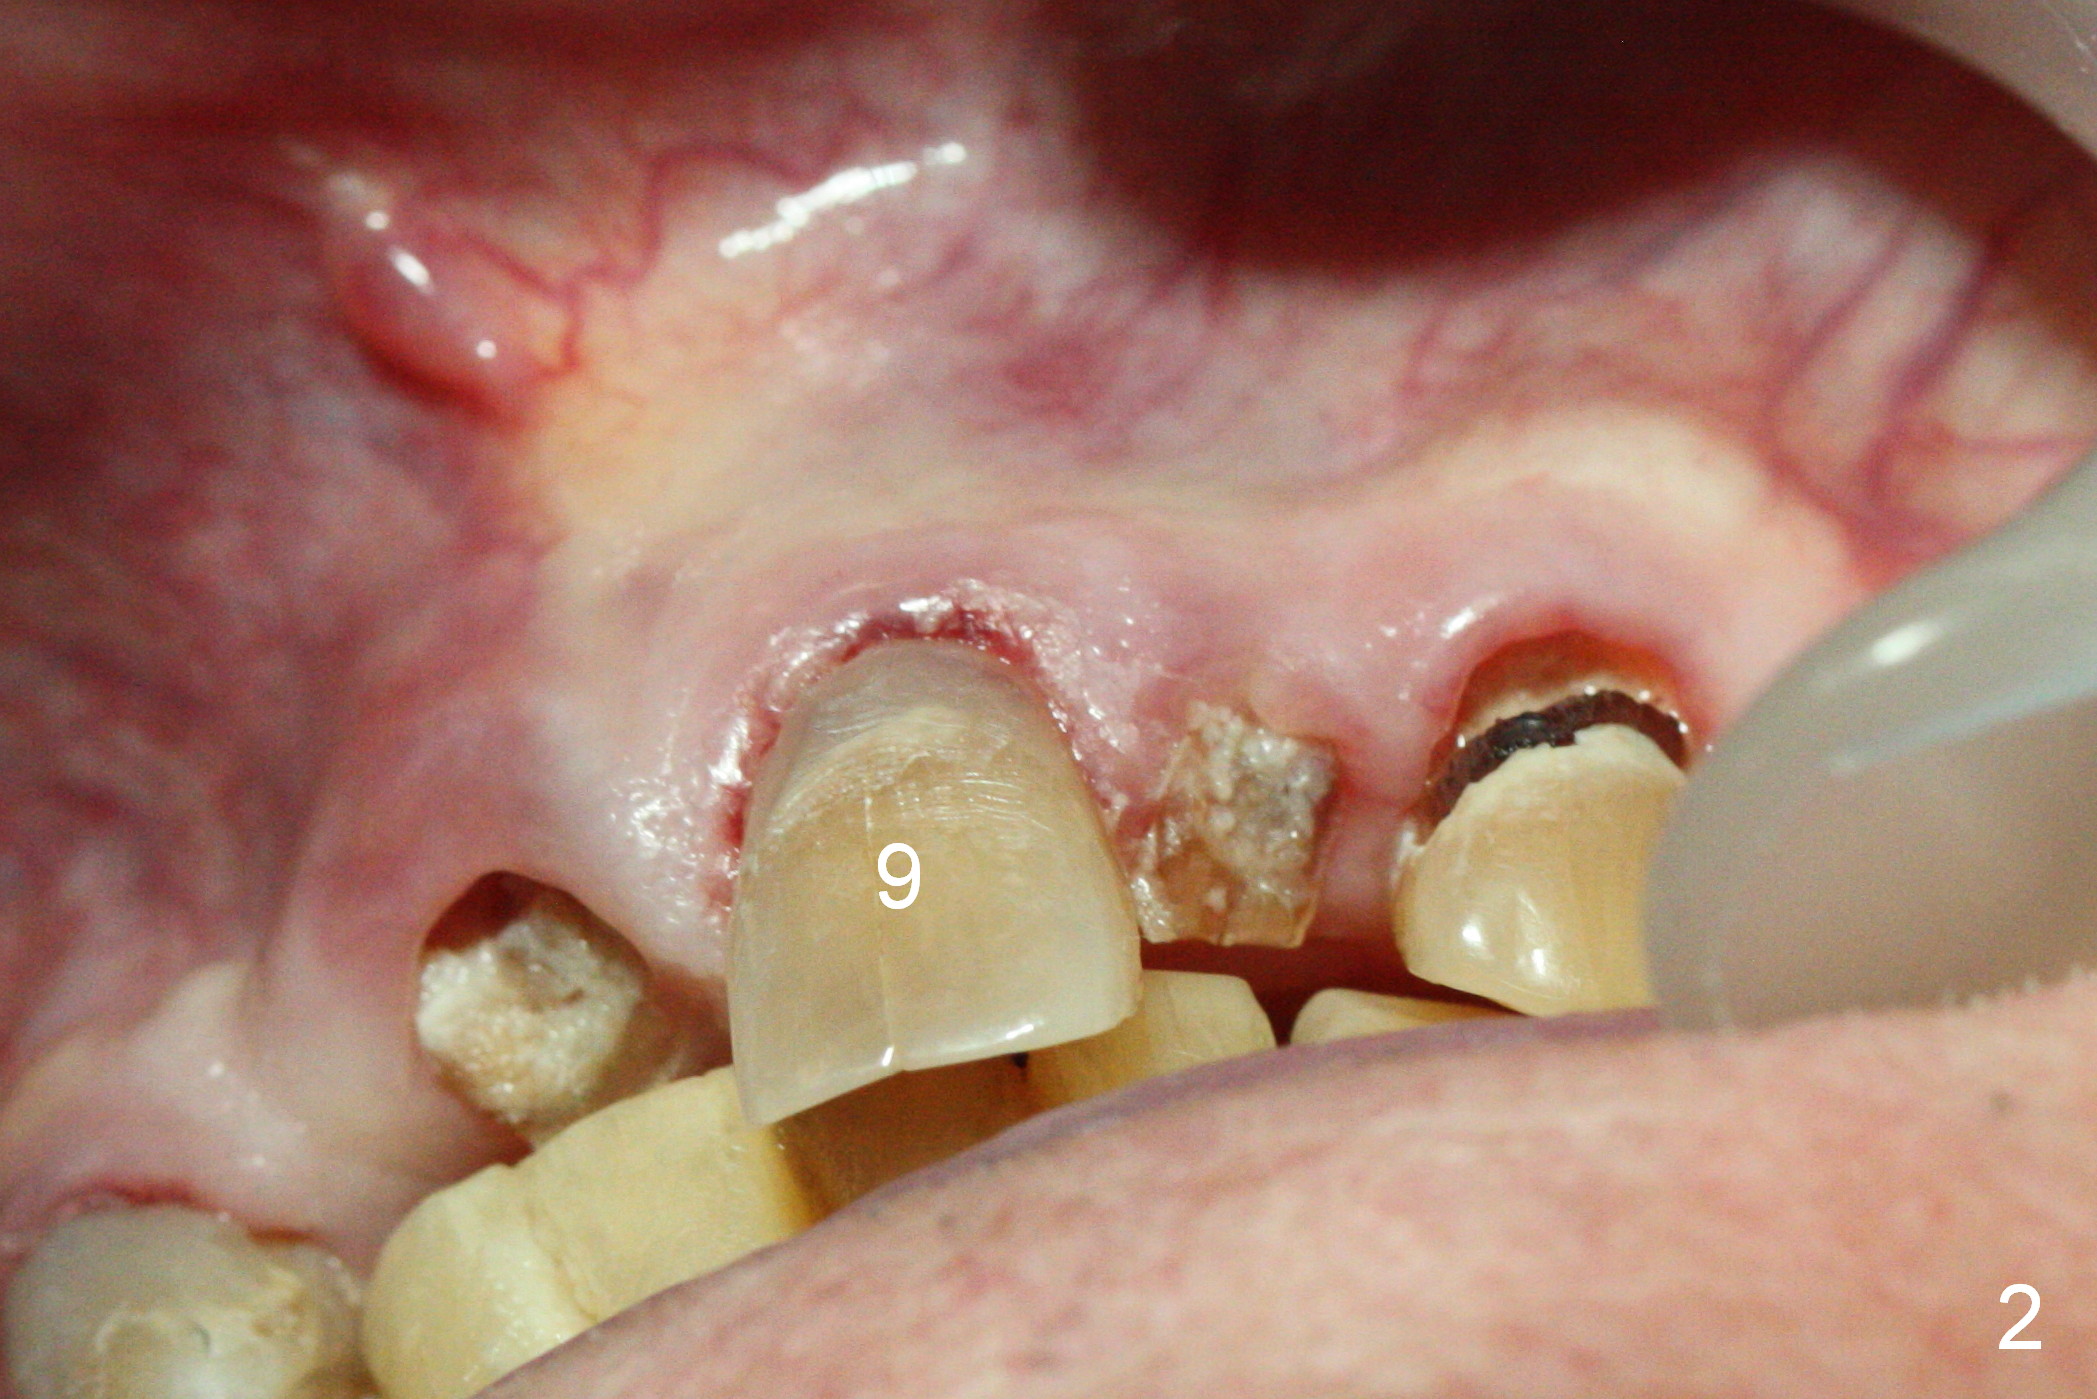

A 88-year-old man (CA) has severe xerostomia-induced caries. After caries control, implants will be placed at #7, 8 and 10 with narrow mesiodistal width (Fig.1,2). Note concavity at the apical buccal plate (*). To prevent perforation, an angled 1-piece implant will be used at #7. Try to place the implant in the middle of the alveolus (digital palpation while drilling) and let the angled abutment take care of the trajectory. To preserve papillae, flapless approach is going to be adopted. Initial depth at these sites will be 12,14 and 14 mm, respectively (Fig.3,4). Use Boley gauge to measure widths of the root to determine the diameter of the implant.